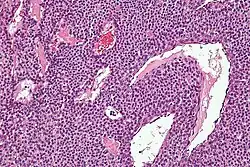

| Micrograph of a glomus tumor. H&E stain. | |

Histologically, glomus tumors are made up of an afferent arteriole, anastomotic vessel, and collecting venule. Glomus tumors are modified smooth muscle cells that control the thermoregulatory function of dermal glomus bodies. As stated above, these lesions should not be confused with paragangliomas, which were formerly also called glomus tumors in now-antiquated clinical usage. Paragangliomas do not arise from glomus cells, but glomus tumors do.